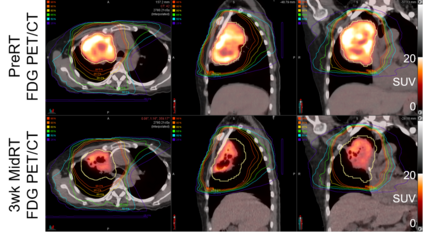

Boosting Trees are one of the most successful statistical learning approaches that involve sequentially growing an ensemble of simple regression trees (i.e., "weak learners"). However, gradient boosted trees are not yet available for spatially correlated data. This paper proposes a new gradient Boosted Trees algorithm for Spatial Data (Boost-S) with covariate information. Boost-S integrates the spatial correlation structure into the classical framework of gradient boosted trees. Each tree is grown by solving a regularized optimization problem, where the objective function involves two penalty terms on tree complexity and takes into account the underlying spatial correlation. A computationally-efficient algorithm is proposed to obtain the ensemble trees. The proposed Boost-S is applied to the spatially-correlated FDG-PET (fluorodeoxyglucose-positron emission tomography) imaging data collected during cancer chemoradiotherapy. Our numerical investigations successfully demonstrate the advantages of the proposed Boost-S over existing approaches for this particular application.